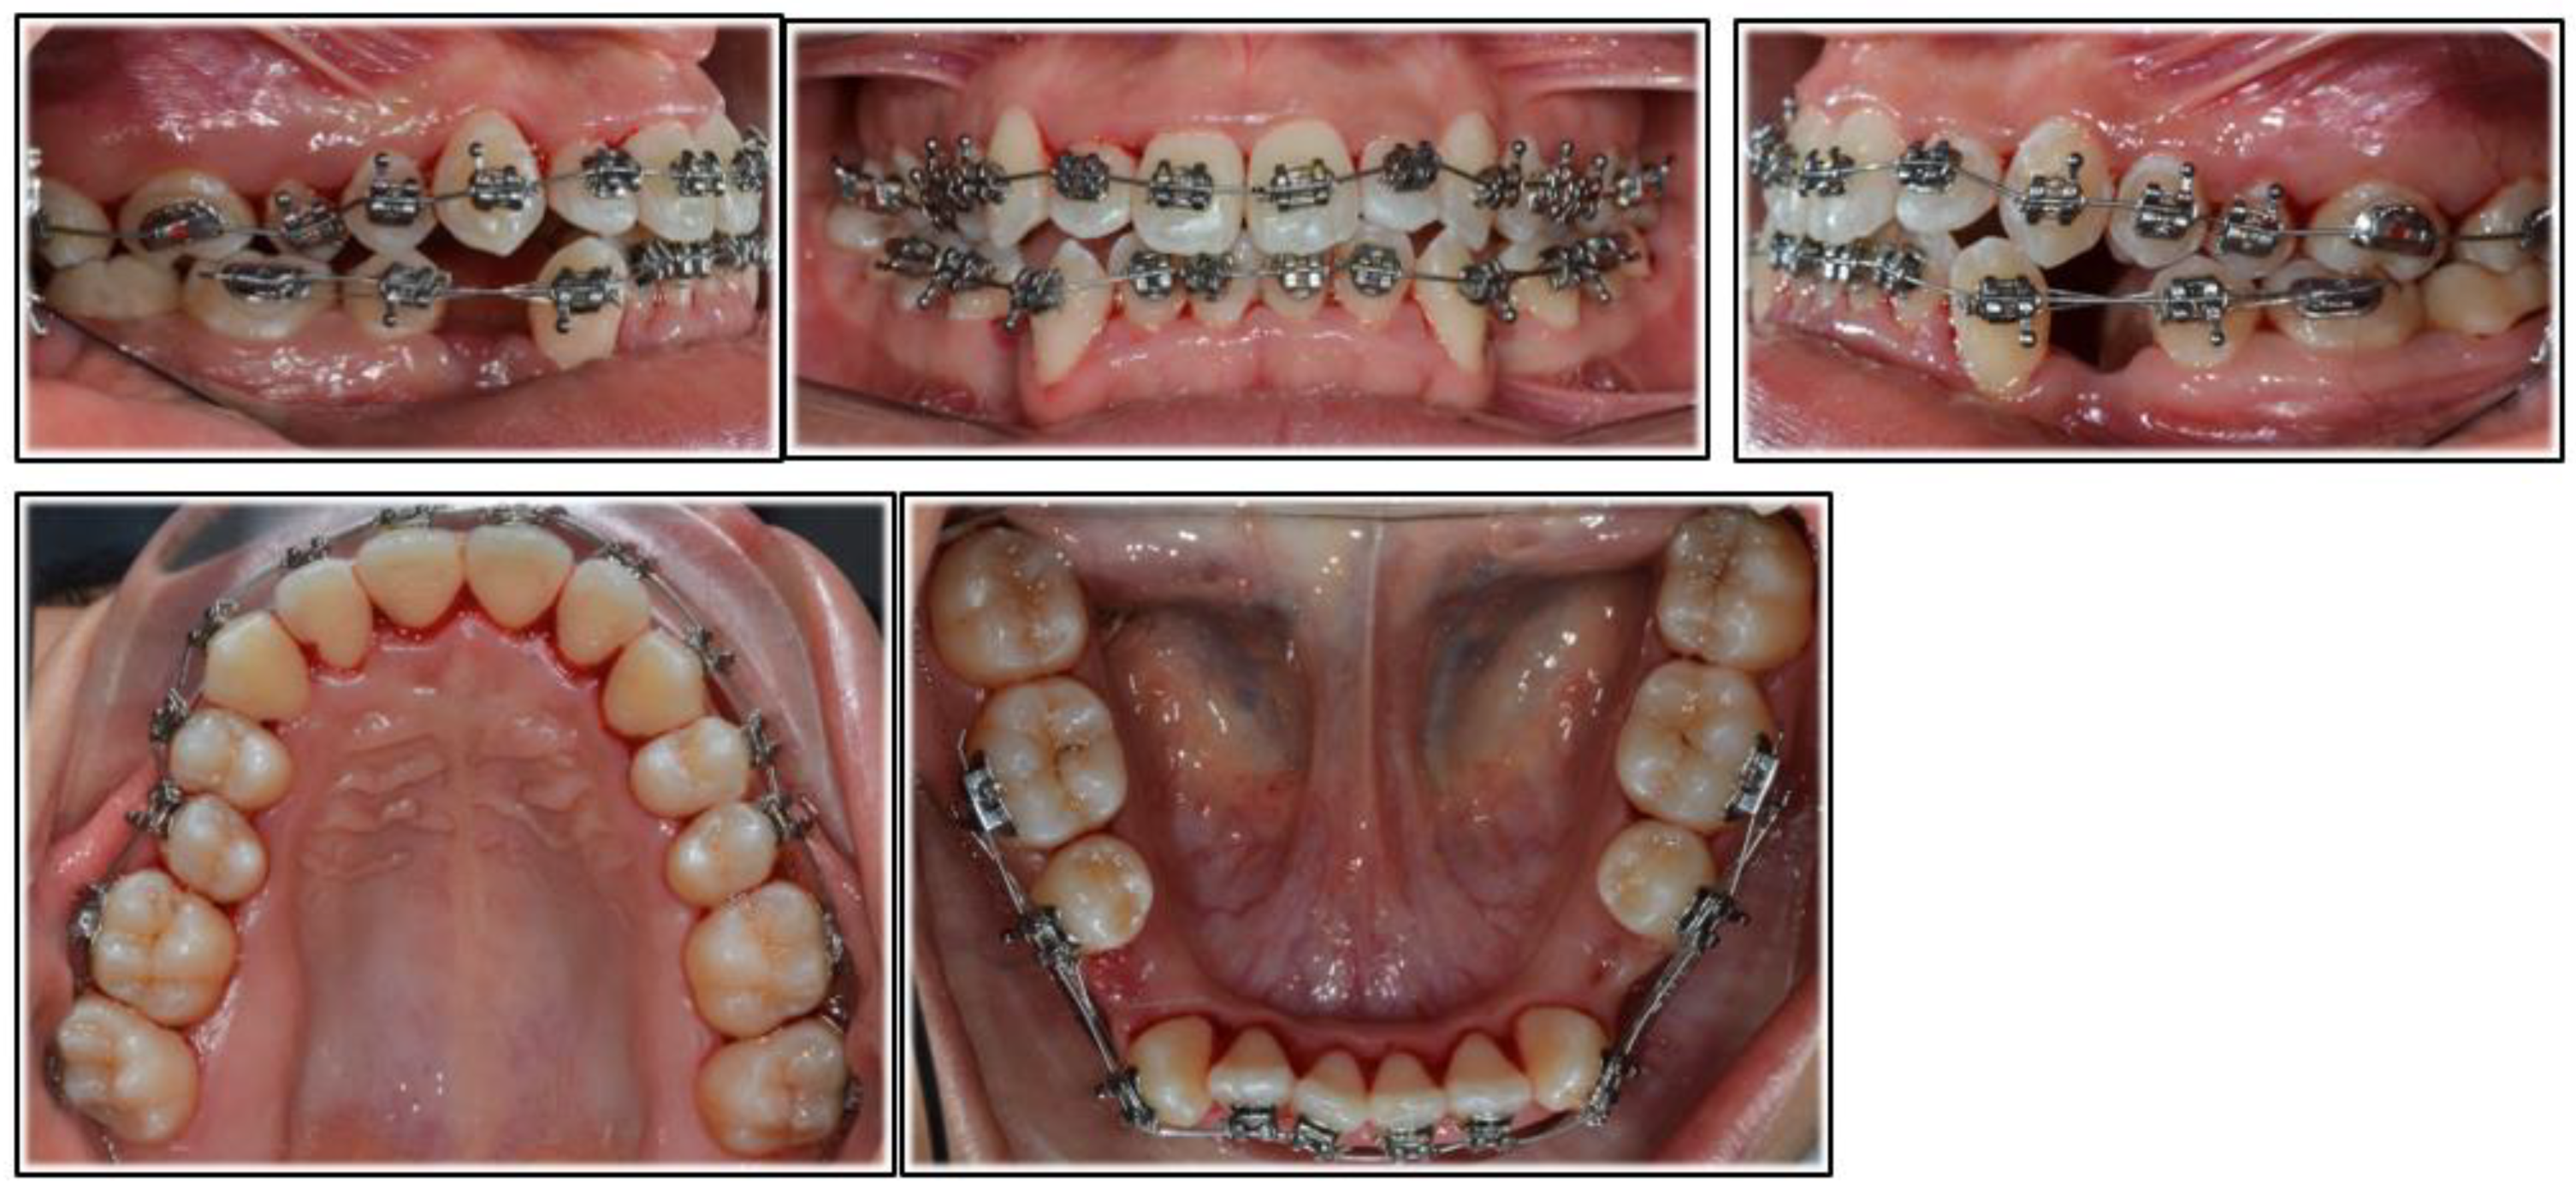

2. Case Report

2.2. Treatment Progress